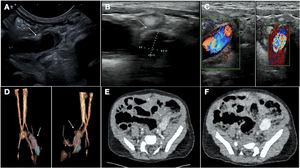

We present the case of a boy aged 15 months with a prenatal diagnosis of pulmonary atresia with intact ventricular septum who underwent pulmonary valve perforation and balloon valvuloplasty with an 8 mm balloon at 9 days post birth (Fig. 1A–D; Appendix B, videos 1–3). At 30 days, due to persistent desaturation, the decision was made to perform percutaneous ductal stenting, since this was less invasive compared to other techniques used to increase pulmonary flow. The procedure, guided by ultrasound, consisted in the delivery, via the left femoral artery and using a 5 F introducer, of a drug-eluting stent (Onyx Frontier, Medtronic, USA) measuring 4.5 × 12 mm to the ductus arteriosus (Fig. 1E and F; Appendix B, videos 4 and 5). Five days after the procedure, the patient experienced vomiting, and the abdominal ultrasound scan used for initial assessment revealed a mass in the left groin, with subsequent Doppler and angio-CT scans allowing visualization of a pseudoaneurysm at the level of the left common iliac artery (Fig. 2A–F).

Due to the risks involved in surgical intervention and the scarcity of the evidence on endovascular treatment in newborns, currently limited to isolated case reports,1,2 the patient was managed conservatively with close clinical and radiological monitoring. Fifteen months later, the patient remains asymptomatic and has started to stand and walk without any problems associated with the pseudoaneurysm, which has exhibited progressive reduction in follow-up imaging (Fig. 3A and B). We present this case to demonstrate the feasibility of the conservative management of vascular complications in pediatric patients, an approach that requires very close clinical and radiological monitoring in experienced centers.